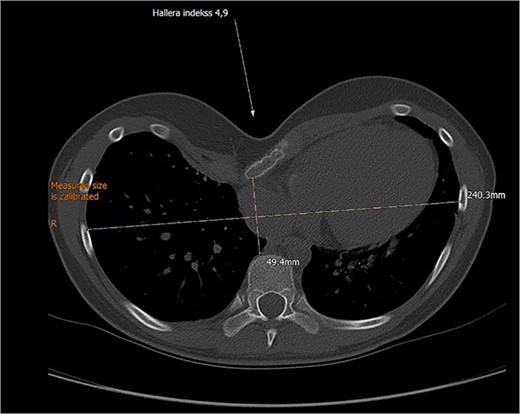

A 12-year-old female patient with severe PE was admitted for an elective MIRPE. Upon exertion, she complained of shortness of breath and feeling of pressure in the chest. Cosmetic concerns were expressed by the patient and her family. Inspection and palpation of the thoracic region revealed a deep conical depression of the chest wall. Preoperative electrocardiogram, echocardiography and pulmonary function tests at rest were normal. Computed tomography (CT) showed a Haller index 4.9, indicating cardiac displacement to the left and rotation of the sternum to the right by 35° (Fig. 1).

Preoperative computed tomography demonstrating severe pectus excavatum with Haller’s index 4.9.